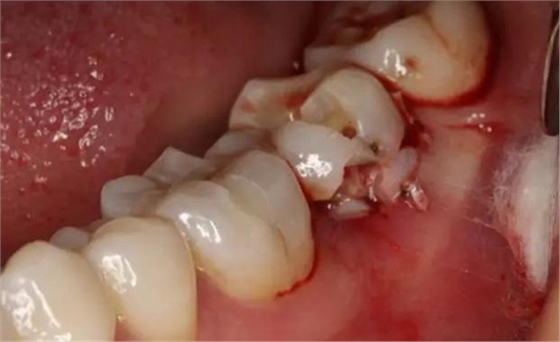

圖6.微創(chuàng)挺拔除37。

圖7. 37牙冠碎裂。多生牙壓迫吸收程度嚴重。